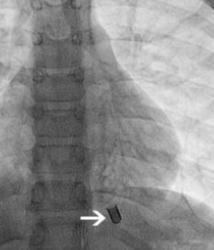

胸片显示左下肺叶的后背段有异物存在。在异物停留部位有支气管扩张的改变,说明有慢性炎症。

鉴于异物所处的部位过深,单独应用肺部介入技术取出异物难度过大,便决定联合心脏介入技术进行治疗。全麻并插入6.5mm的支气管导管。将2.8mm的支气管镜连接双轴旋转接头,在透视介导下,探查左主支气管直至不能深入。此时支气管镜距离异物仍有几毫米。撤出纤维支气管镜后,将4-Fr的Terumo指引导管和0.018英寸的Hi-Torque Flex-T导丝通过旋转接头送入。在透视介导下,导管很容送到了异物周围。之后将导管替换为6-Fr JR-4的大口径指引导管。